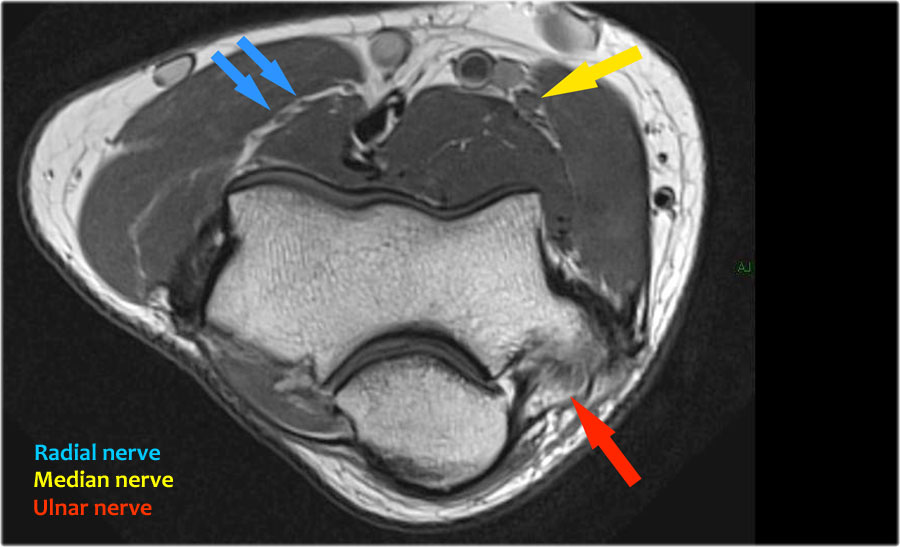

Radial nerve

Dây thần kinh quay có thể được xác định rõ nhất ở mức chỏm xương quay, nơi có thể quan sát thấy các nhánh nông và nhánh sâu trong ống xương quay (mũi tên).

This is a very consistent place to find the radial nerve.

Các nhánh quay sâu tạo thành thần kinh gian cốt sau xuyên qua cơ ngửa tại cung Frohse (mũi tên).